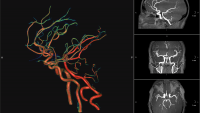

- 3D laboratory with dedicated workstations for recons: AW, Tera Recon and Vitrea

Residents and fellows receive strong education and training in all aspects of neuroradiology including magnetic resonance imaging, computed tomography, myelography, arteriography, biopsies and interventional neuroradiology. There are opportunities to learn advanced CNS imaging techniques such as quantitative MR spectroscopy, DSC perfusion MRI, functional MRI (fMRI) and diffusion tensor imaging.